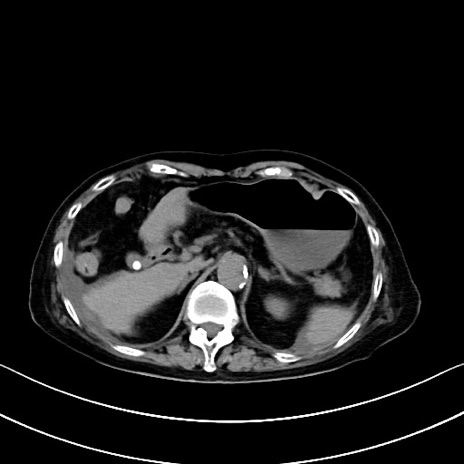

症例40(横断像)他院1日前

横断像

他院CT